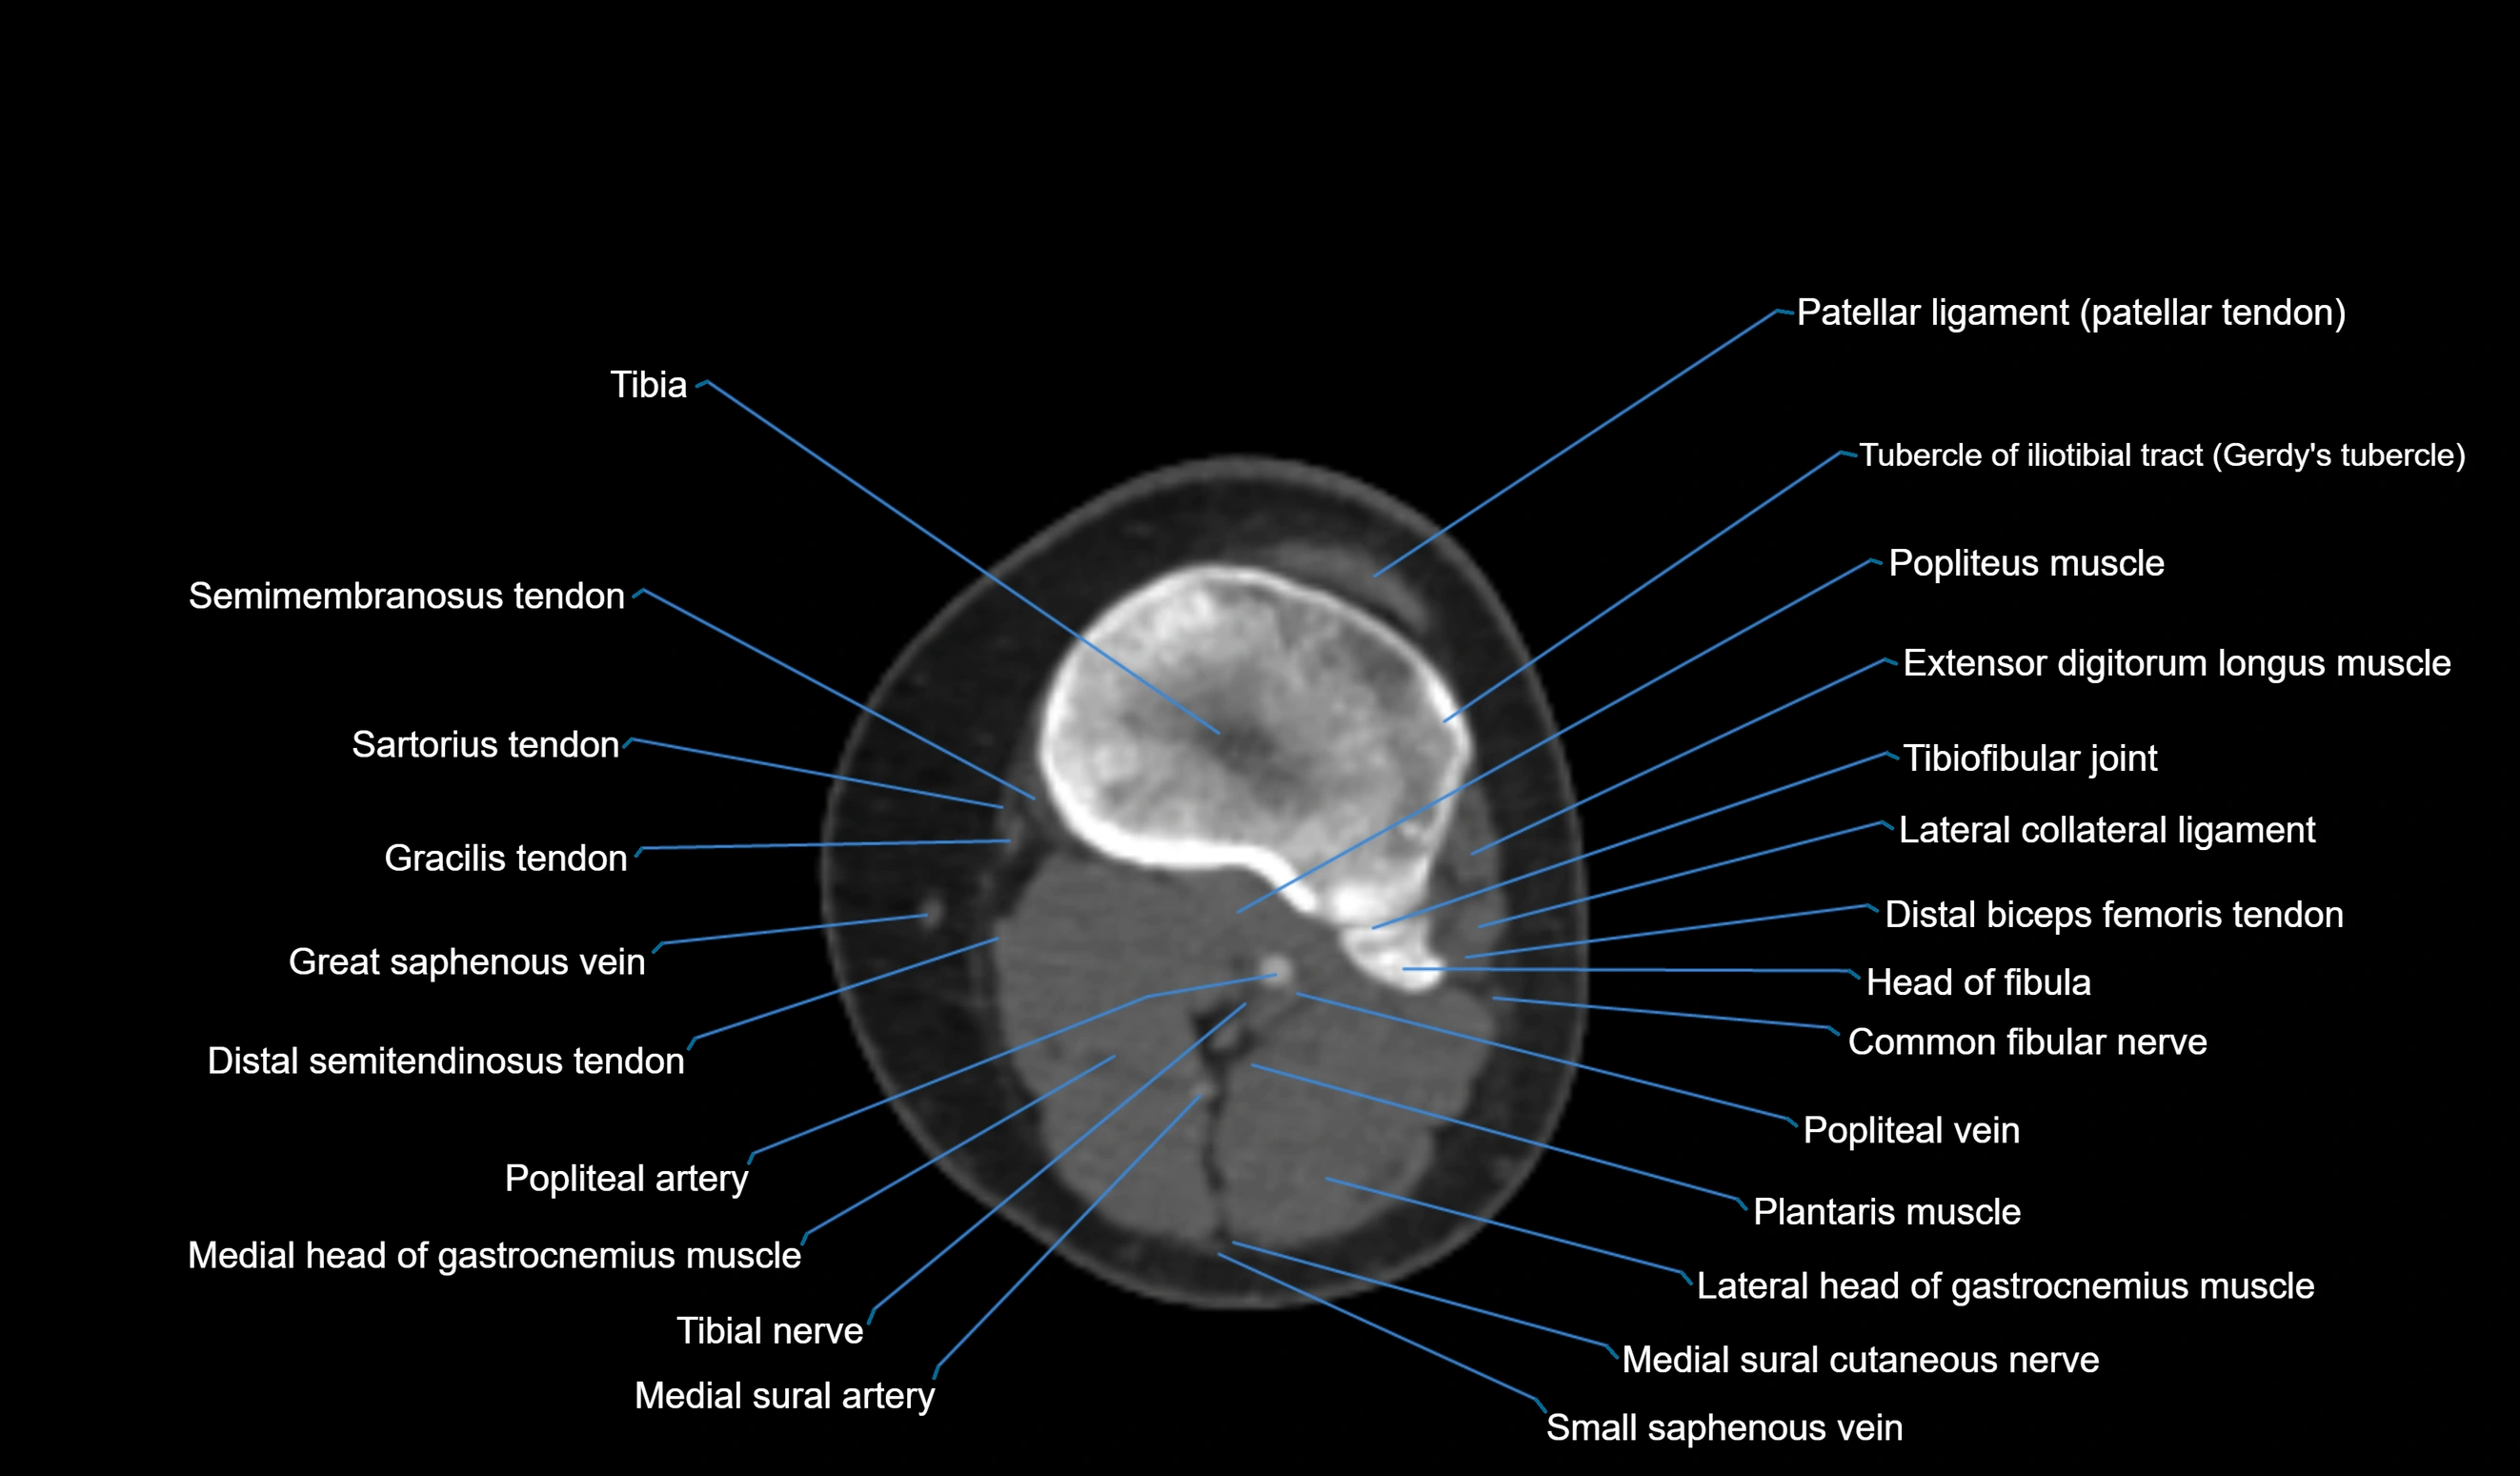

- Common fibular nerve

- Distal biceps femoris tendon

- Extensor digitorum longus muscle

- Head of fibula

- Lateral collateral ligament

- Lateral head of gastrocnemius muscle

- Medial sural cutaneous nerve

- Plantaris muscle

- Popliteal artery

- Popliteal vein

- Popliteus muscle

- Small saphenous vein

- Superior tibiofibular joint

- Tibia

- Tibial nerve

- Tibiofibular joint (proximal)

- Tubercle of iliotibial tract